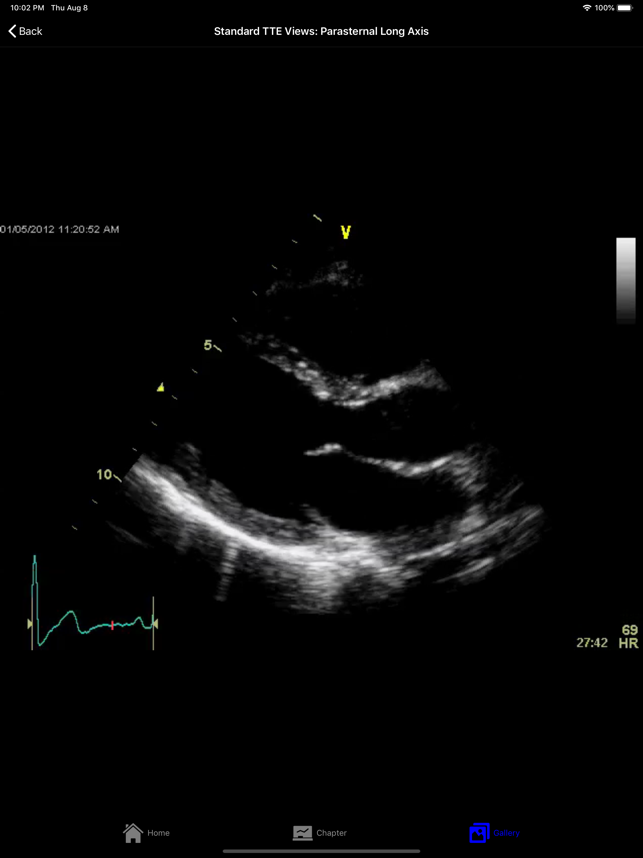

EchoSource (from the creators of ECGsource and CathSource) is a medical reference devoted exclusively to echocardiography. Developed by practicing cardiologists for both specialists and trainees in the field of cardiovascular disease, EchoSource offers the following content:* Searchable index of specialized topics including: History of EchocardiographyTransthoracic Echo – Learning the ProcedureTransesophageal Echo – Learning the ProcedureStandard Transthoracic Echocardiography ViewsStandard Transesophageal Echocardiography ViewsHemodynamics: Doppler OverviewHemodynamics: Color Flow ImagingHemodynamics: Transvalvular GradientsHemodynamics: Intracardiac PressuresHemodynamics: Cardiac Flow & the Continuity EquationHemodynamics: Proximal Isovelocity Surface Area (PISA)Left Ventricle: Systolic FunctionLeft Ventricle: Diastolic Function Valvular: Aortic StenosisValvular: Aortic RegurgitationValvular: Mitral StenosisValvular: Mitral RegurgitationValvular: Pulmonic StenosisValvular: P